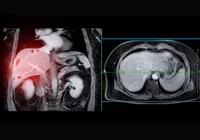

Hepatocellular carcinoma (HCC), the most common type of primary liver cancer, poses unique diagnostic and therapeutic challenges due to its complex biological behaviour. Intratumoural fat—fat deposits within the tumour tissue—has become an area of focus as it appears to be associated with different prognostic outcomes. MRI imaging has proven essential for non-invasive assessment, allowing detailed insights into fat patterns within tumours. However, the prognostic significance of intratumoural fat in HCC is debated. A recent review published in  Radiology examines a comprehensive cohort study on general and homogeneous intratumoural fat roles in HCC, covering patient outcomes in both Asian and European contexts.

In this study, differences in fat patterns were analysed across two patient cohorts—one from East Asia, primarily associated with hepatitis B, and another from Western Europe, where metabolic dysfunction–associated fatty liver disease was more common. Fat-containing tumours in both cohorts often exhibited such characteristics as non-peripheral washout, enhancing capsules and mosaic architecture, all visible on MRI scans. However, a notable divergence was observed in fat frequency and impact across the cohorts. For Asian patients, intratumoural fat often aligned with the steatohepatitic subtype of HCC, showing a higher incidence of non-aggressive features. These results suggest that MRI-assessed intratumoural fat, while significant in both cohorts, may represent a complex of factors influenced by distinct underlying health conditions.

MRI assessment allows for further categorisation of intratumoural fat patterns into homogeneous (uniform) and heterogeneous (mixed) distributions. The study found that homogeneous intratumoural fat might be associated with more favourable tumour biology, particularly in Asian patients. Homogeneous fat distribution, which was identified in 15% of Asian patients and 14% of European patients, was linked with longer recurrence-free survival (RFS) and overall survival (OS) within the Asian cohort. These patients also exhibited lower incidences of vascular invasion and smaller tumours, which often translated into less aggressive tumour behaviour.